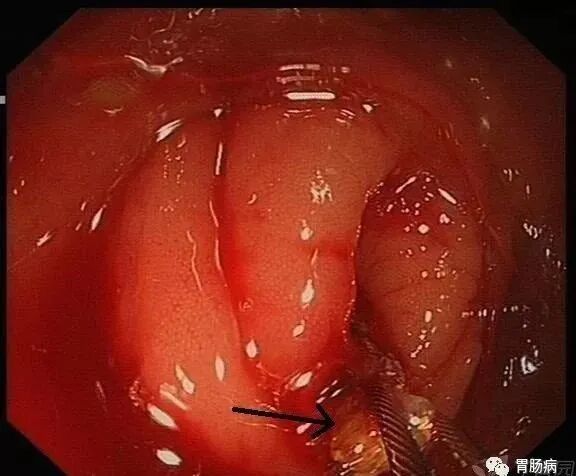

(下图可见白色脓液)

当黄斑马导丝及导管置入阑尾腔时,可见脓性分泌物涌出。随之进行阑尾腔冲洗;